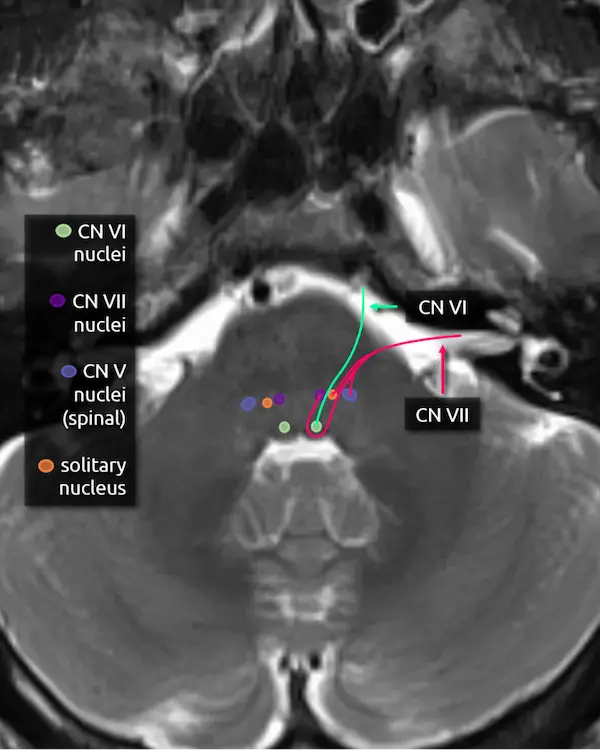

5. Abducens nucleus (CN VI)

The abducens nucleus is located in the dorsal pons at the level of the internal auditory canals. The facial colliculi are the two bumps along the dorsal surface of the pons at this level, which are formed by the facial nerve coursing over the abducens nucleus.

6. Abducens nerve (CN VI)

The abducens nerve courses anteriorly from the abducens nucleus and exits the ventral pons at the pontomedullary junction. After traversing the prepontine cistern, the nerve enters Dorello's canal, where it is relatively fixed in place. It also has the longest subarachnoid course of the cranial nerves. These two features make it particularly susceptible to stretching-related injury, e.g., in the setting of brain herniation. After Dorello's canal, the nerve enters the cavernous sinus, where it is susceptible to mass effect from space occupying lesions, e.g., a mass or a cavernous internal carotid artery aneurysm.

The abducens nerve innervates the ipsilateral lateral rectus muscle, responsible for eye abduction. Damage will cause horizontal diplopia.

7. Facial nucleus (CN VII)

The facial nucleus is located in dorsal pons anterior to the abducens nucleus and posterior to the medial lemniscus.

8. Solitary nucleus

The solitary nucleus is located lateral to the facial nucleus in the lower pons and extends to the upper medulla. It contributes to the facial, glossopharyngeal, and vagus nerves.

Damage to the solitary nucleus may manifest as decreased taste sensation on the ipsilateral tongue.

9. Spinal nucleus of the trigeminal nerve (CN V)

The spinal nucleus of the trigeminal nerve is the inferior continuation of the main sensory nucleus of the trigeminal nerve (see level 3). It is involved in sensation of the head and face. It receives afferent fibers from the facial, glossopharyngeal, and vagus nerves.

10. Facial nerve (CN VII)

The facial nerve courses posteriorly from the facial nucleus before looping over the ipsilateral abducens nucleus and exiting the anterolateral pons at the pontomedullary junction. It then enters the internal auditory canal with the vestibulocochlear nerve (CN VIII). Four nuclei contribute to the facial nerve; the three listed above, and a fourth called the superior salivary nucleus responsible for parasympathetic fibers located medial to the facial nucleus, not pictured here. The nerve has motor, sensory, and parasympathetic functions: